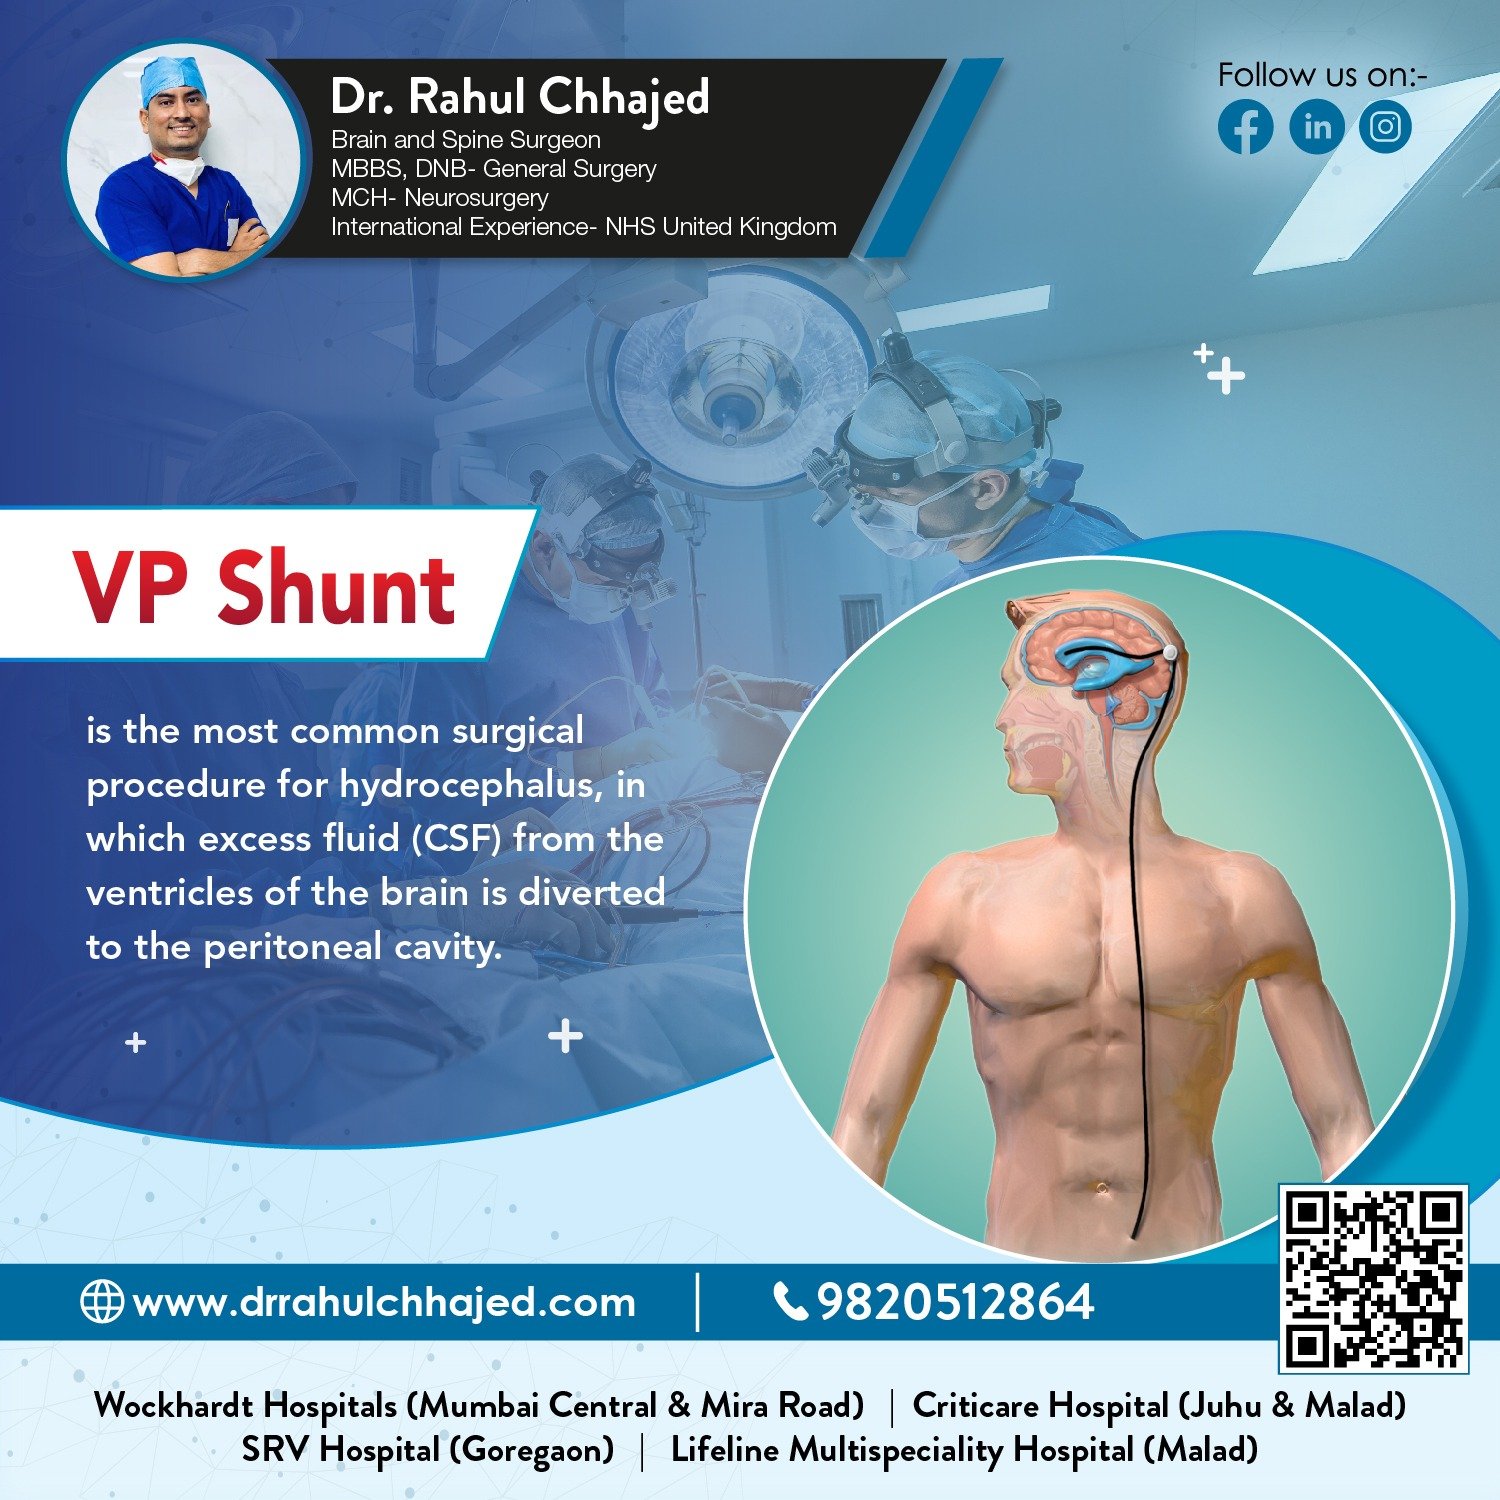

Hydrocephalus Surgery

The most common treatment for hydrocephalus is the surgical insertion of a drainage system, called a shunt. At our practice, we specialize in hydrocephalus surgery, which can relieve the pressure on the brain and help alleviate symptoms.